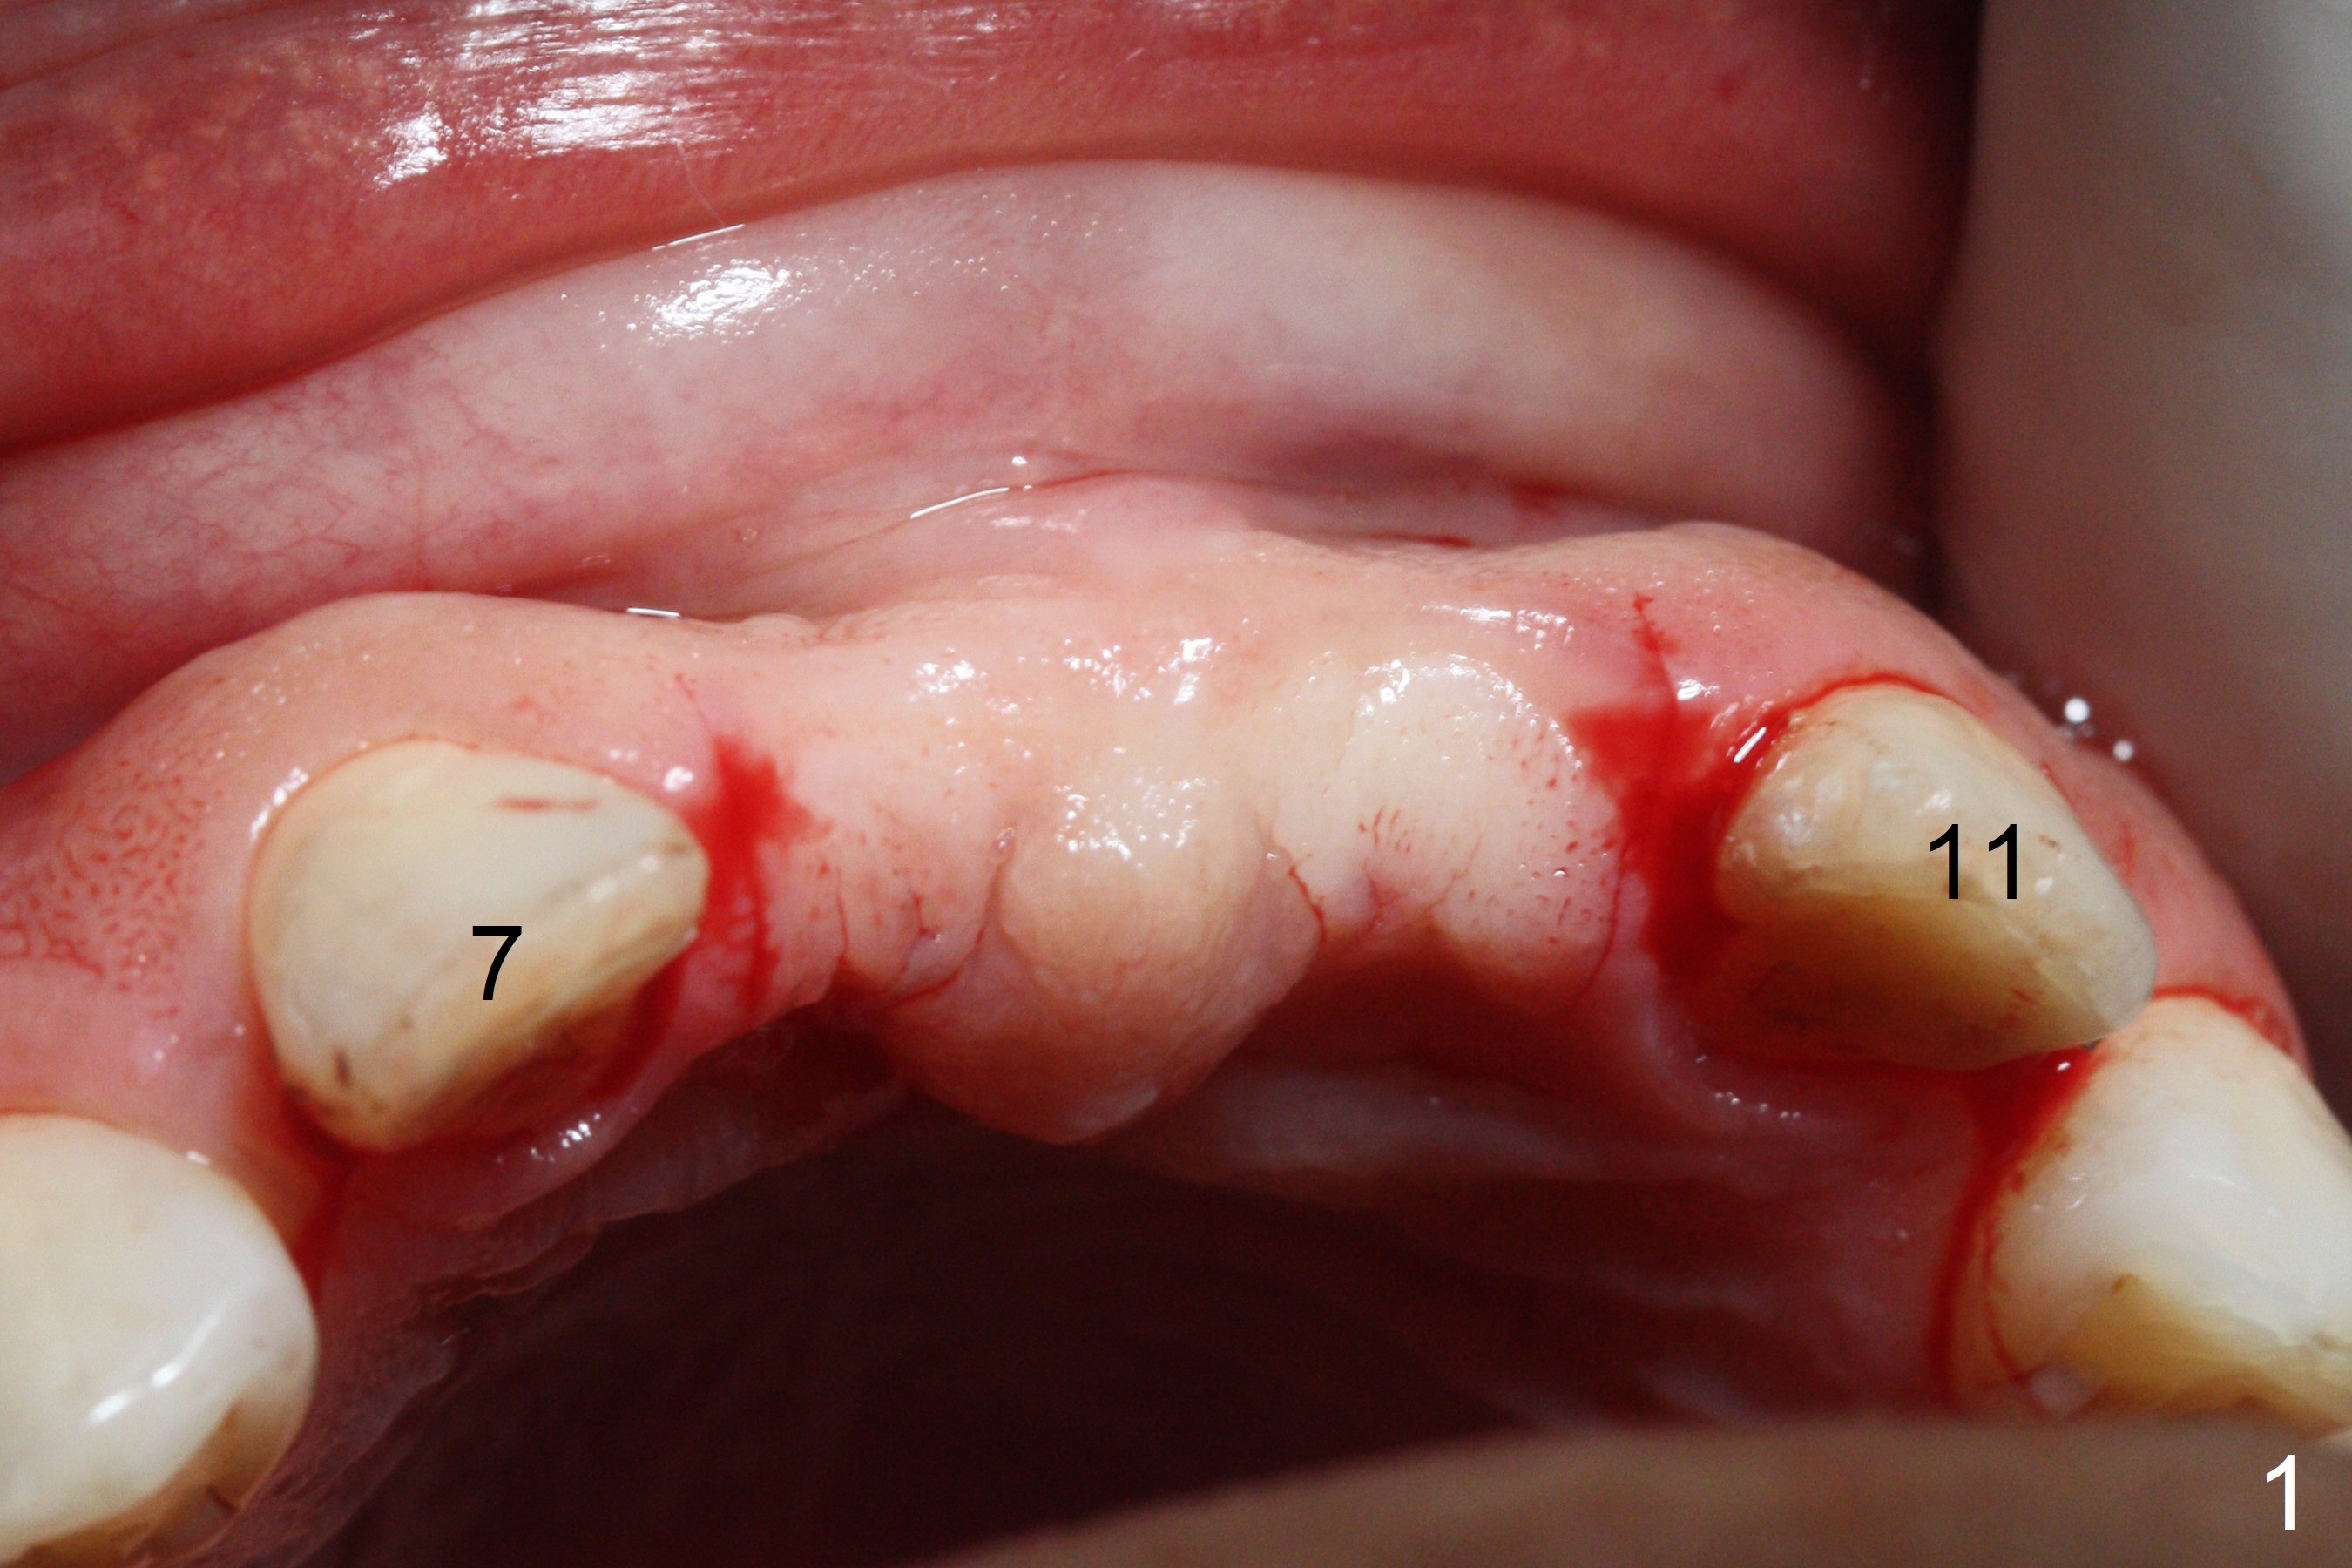

A 45-year-old Spanish woman requests implants to replace #7-10 FPD (Fig.1,2,7). After incision, osteotomy is initiated in the palatal aspect of the crest with 1.2 mm drill and DIO Bone Expanders (E1 (diameter 1.0/1.6 mm),E2 (1.3/2.3 mm), Fig.3,4). Following adjustment of the trajectory (to avoid invasion of the Incisive Canal (Fig.2 *) and use of E3 (1.7/3.1 mm), two of 3.5x11.5 mm HIOSSEN implants are placed with satisfactory stability (Fig.5). With Vanilla graft (Fig.5 *) placed over the palatally-exposed coronal threads, the flaps are approximated (Fig.6). The FPD is recemented temporarily (Fig.7).